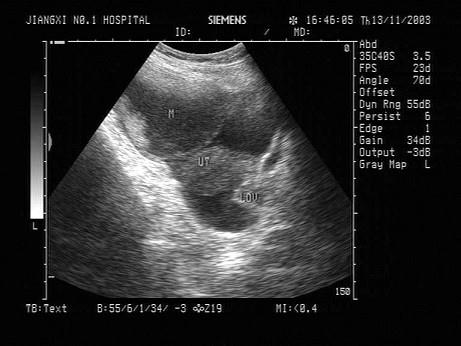

问题 女性,56岁,消瘦、腹部膨隆3月余。妇科检查:盆腔触及包块。超声检查如图,最可能的诊断为?(?)

选项 A.转移性卵巢癌 B.囊腺癌 C.黄体囊肿 D.黄素囊肿 E.囊腺瘤

答案 B